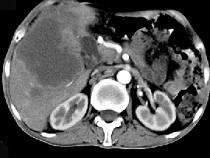

问题 男,49岁,右上腹痛半年,轻度黄疸,AFP阴性,CT检查如图,最可能的诊断为()

选项 A.原发性肝癌 B.胆管细胞癌 C.局灶性脂肪肝 D.肝脓肿 E.肝淋巴管瘤

答案 B